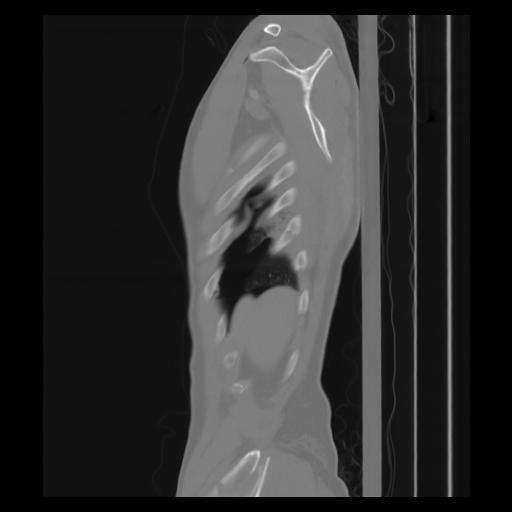

30 CUERPO,CE,Sagittal,3.000,CUERPO,Sagittal,